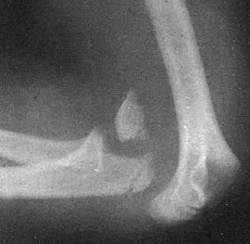

В анамнезе — соответствующая травма. Сустав отёчен и деформирован. На задней поверхности, на расстоянии от плеча, под кожей виден локтевой отросток. Нарушены треугольник и линия Гютера. Предплечье укорочено. Активные и пассивные движения в локтевом суставе отсутствуют, их попытка вызывает острую боль. Отмечается положительный симптом пружинящего сопротивления.

На рентгенограммах в двух проекциях выявлено разобщение сочленяющихся поверхностей плеча и предплечья.